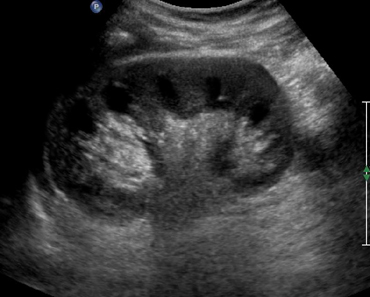

Ультразвуковая диагностика органов живота является достаточно простой процедурой. Врачу потребуется не более 15 минут для исследования всех органов живота. Пациента попросят лечь на спину и оголить туловище. На область живота врач наносит специальный гель, улучшающий визуализацию органов. Для осмотра структур органов брюшной полости используется специальный датчик, захватывающий отраженные ультразвуковые волны.

Во время исследования врач попросит пациента ложиться на бок и иногда на живот. Также пациента могут попросить задержать дыхание или, напротив, дышать глубоко. Такие манипуляции помогают лучше рассмотреть исследуемые органы.

В дополнении к обычной УЗИ-диагностике врач может применять допплерографию для исследования сосудов. Это особенно важно для оценки состояния брюшной аорты.